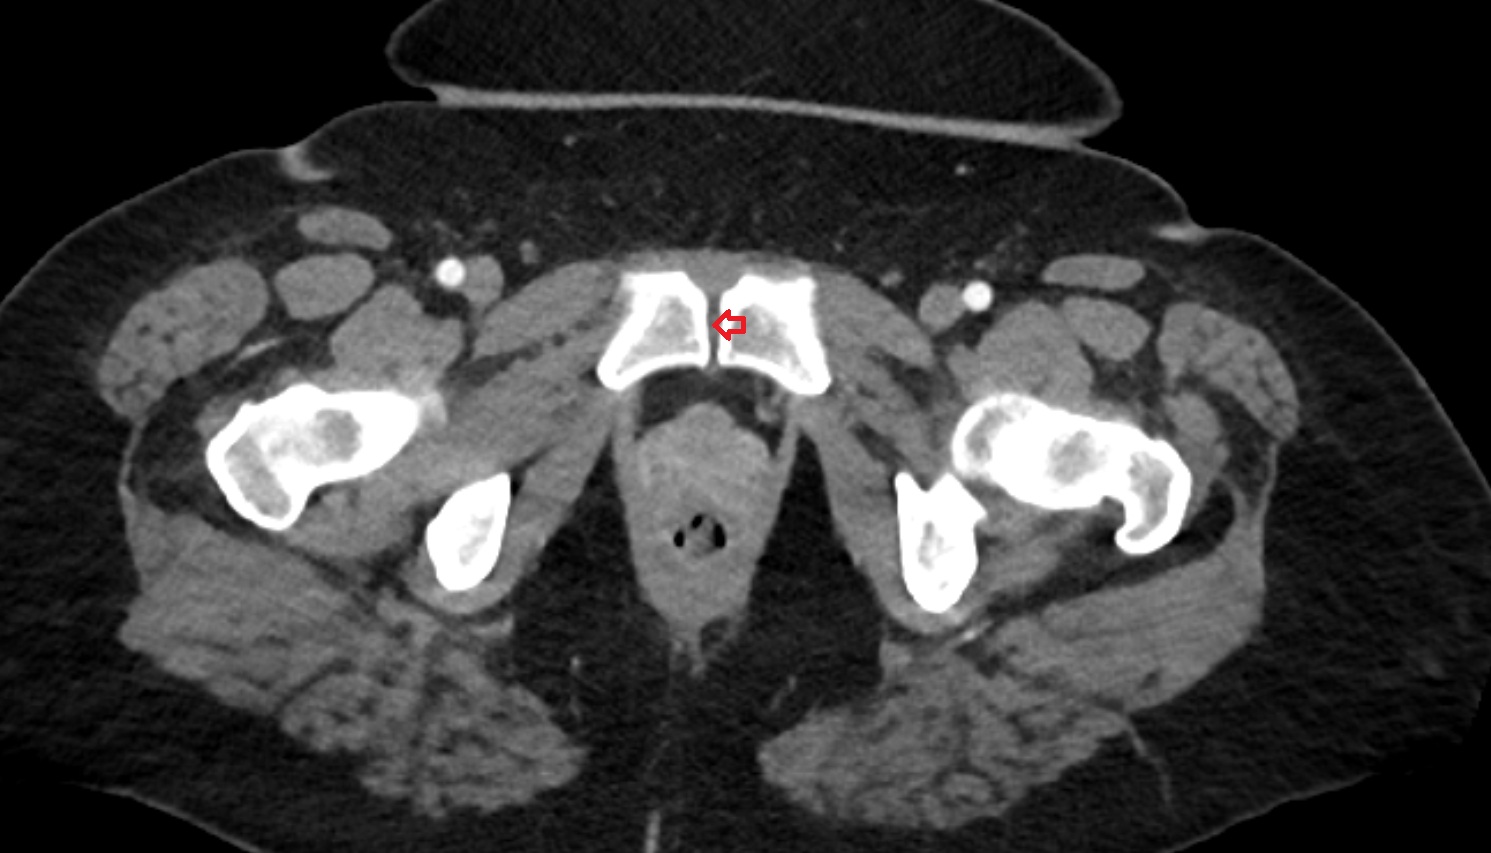

- Peripheral zone of prostate

- Anterior Fibromuscular Stroma of prostate

- Central zone of prostate

- Transitional zone of prostate